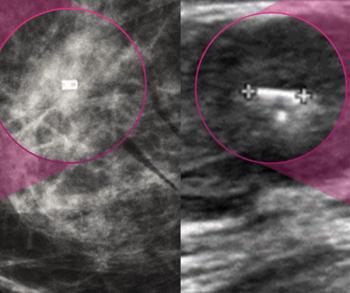

Mammography Study Reveals Limitations with DBT in Women with Extremely Dense Breasts